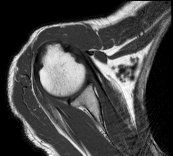

Axial:

![]() |